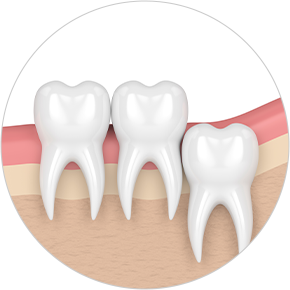

• Horizontally

impacted wisdom tooth

• Angulated

• Vertically